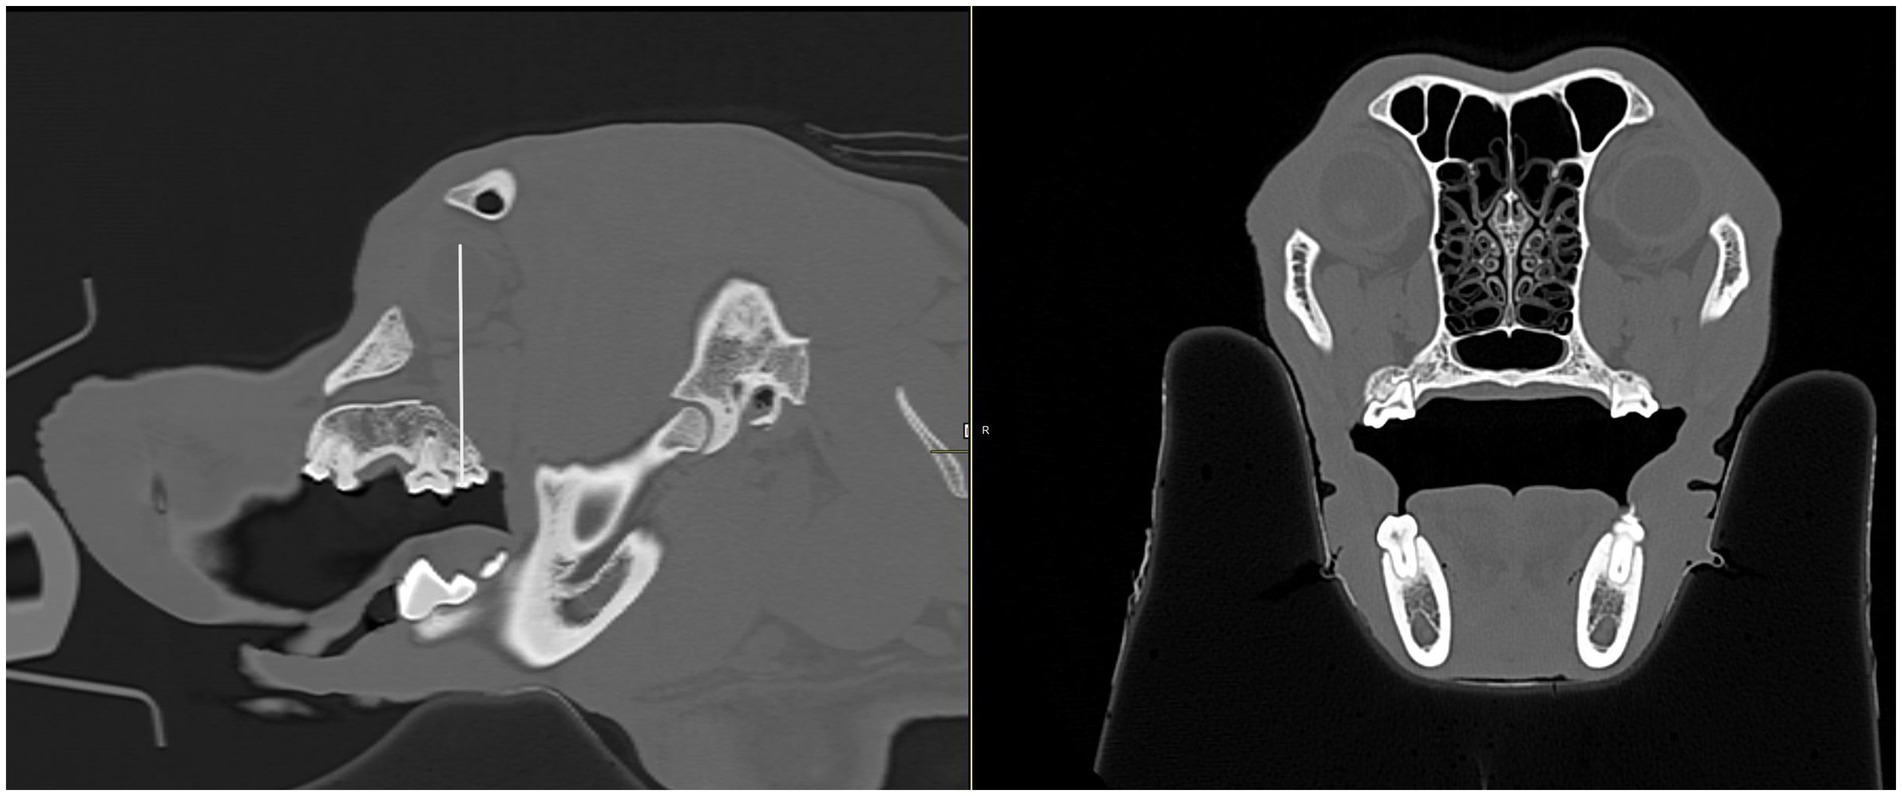

Figure 10

Four-panel CT scans of a dog and cat skull. Panel A shows a saggital view with a measurement of 37 millimeters from the opening of the infraorbital foramen to the eye in a dog skull. Panel B displays another lateral view of a cat's skull with 13 millimeters measured from the infraorbital foramen to the eye. Panel C shows a saggital and transverse CT scan of a dog skull with a measurement taken from the hard palate to the eye. Panel D shows a saggital and transverse CT view of a cat skull with a measurement taken from the hard palate to the eye.

Figure 10. CT images showing measurements from the infraorbital foramen-to-globe and hard palate-to-globe distances in the cat and dog. Measurements were taken to simulate accidental globe puncture during an infraorbital nerve block (A,B), maxillary nerve block using the modified infraorbital approach (A,B), and the caudal maxillary nerve block (C,D). (A) This sagittal CT image shows the measurement, in millimeters, from the infraorbital foramen to the closest surface of the globe (white line) in a dog. (B) This sagittal CT image shows the measurement, in millimeters, from the infraorbital foramen to the closest surface of the globe (white line) in a cat. (C) Sagittal (left) and transverse (right) CT images of a dog skull showing the measurement, in millimeters, from the caudal border of the palate, immediately caudal to the left maxillary second molar tooth, to the closest surface of the globe (white line). (D) Sagittal (left) and transverse (right) CT images of a cat skull showing the measurement, in millimeters, from the caudal border of the palate, immediately caudal to the left maxillary first molar tooth, to the closest surface of the globe (white line).

To simulate accidental globe puncture during the intraoral caudal maxillary nerve block, measurements were taken from the caudal border of the palate, immediately caudal to the maxillary second molar tooth in dogs and maxillary first molar tooth in cats, to the closest surface of the globe (palate-to-globe) using sagittal and transverse views (Figures 10C,D). In dogs and cats with a last mandibular molar tooth, the distance from the distal crown surface of the last mandibular molar tooth to the first CT slice with an open mandibular foramen was recorded using the transverse view (Figures 11AD). Accurate distance measurements from the last mandibular molar tooth to the mandibular foramen were not possible on the sagittal view due to the angulation of the mandible. Root length determination for the distal buccal root of the maxillary first molar tooth in the dogs was measured from the cementoenamel junction to the root apex (Figure 12A). Root length determination for the distal buccal root of the maxillary second molar tooth was measured from the horizontal pulp horn to the root apex (Figure 12B). The cementoenamel junction was not as discernible on the maxillary second molar tooth of the dog, so the horizontal pulp horn was used instead. If the distal buccal root length of the maxillary second molar tooth was not visible on a single transverse slice, then the palatal root was measured instead using the technique described in the previous sentence (Figure 12C). All measurements were collected and recorded separately for the left and right sides. Results were grouped and placed in tables according to their use in clinical practice. Minimum and mean distance values of the infraorbital foramen-to-globe, left and right maxillary first and second molar tooth root apex-to-globe, and palate-to-globe distance values in dogs were grouped (Table 1). Minimum and mean infraorbital foramen-to-globe, left and right maxillary fourth premolar tooth root apex-to-globe, and palate-to-globe distance values in cats were grouped (Table 2). Values ≤2.8 mm were highlighted in gray. Minimum, mean, and standard deviation for infraorbital canal length, infraorbital foramen width and height, and percent of animals with a bifurcation of the infraorbital canal for all cats and dogs were grouped (Table 3). Mean distances from the distal crown surface of the last mandibular molar tooth to the mandibular foramen, and palate-to-maxillary foramen for all dogs and cats were grouped (Table 4). The percentage of distal buccal roots fused with the palatal root, and root length measurements for the maxillary first and second molar teeth in dogs were grouped (Table 5). The percentage of teeth in which the globe was centered over was determined for each body weight and skull type (Table 6), with the first and second highest percentage points highlighted in gray. Results of the most likely position of the eye were recorded for 28 dolichocephalic dogs ≤10 kg, 43 dolichocephalic dogs ≥11 kg, 56 mesocephalic dogs ≤5 kg, 56 mesocephalic dogs of 6–10 kg, 64 mesocephalic dogs ≥11 kg, 62 brachycephalic dogs ≤10 kg, and 62 brachycephalic dogs ≥11 kg (Table 6). Results were recorded for 62 MCat and 16 BCat cat eyes (Table 6). Mean, median, mode, minimum, maximum, and standard deviation of the globe diameter for all cats and dogs were grouped (Table 7). Results were calculated for 28 dolichocephalic dogs ≤10 kg, 43 dolichocephalic dogs ≥11 kg, 63 mesocephalic dogs ≤5 kg, 60 mesocephalic dogs of 6–10 kg, 64 mesocephalic dogs ≥11 kg, 62 brachycephalic dogs ≤10 kg dog eyes, 62 brachycephalic dogs ≥11 kg dog eyes, and 62 MCat and 16 BCat cat eyes. Minimum and mean infraorbital canal length, infraorbital foramen-to-globe, and recommended safe catheter or needle insertion length, for the infraorbital and modified infraorbital approach to the maxillary nerve blocks, were calculated for all cats and dogs (Table 8). All dogs below the mean infraorbital length standard deviation value for infraorbital canal length were considered “extreme brachycephalic” by the authors and included French bulldogs and pugs (four animals in total). The authors observed that French bulldogs, pugs, and Boston terriers had similarly shorter infraorbital canal mean lengths of 2–9 mm, across both ≤10 kg and ≥11 kg brachycephalic weight categories. Boston terriers, French bulldogs, and pugs were pooled together in a group labeled “extreme brachycephalic” for a total of 20 animals (14 French bulldogs, 2 pugs, and 4 Boston terriers), and their values are reported in the second-to-last row of Table 8. Minimum and mean infraorbital canal length and infraorbital foramen-to-globe length distances were recalculated for the brachycephalic dogs ≥11 kg dog group, with extreme brachycephalic dogs removed, to reflect a more accurate representation of the infraorbital canal lengths in these groups (Table 8). Groups where both the minimum infraorbital canal length and infraorbital foramen-to-globe distances were less than 10 mm were highlighted in gray to indicate that extreme caution should be used.

The ability to draw a straight line from the infraorbital foramen to the globe was recorded as a percentage for all cat and dog groups (Table 9). This was possible through the infraorbital canal in 100% of cats, and dolichocephalic dogs ≤10 kg, 95% of mesocephalic dogs ≤5 kg and 81% of mesocephalic dogs of 6–10 kg, 44% of mesocephalic dogs ≥11 kg, 40% brachycephalic dogs ≤10 kg, 16% of brachycephalic dogs ≥11 kg, 58% dolichocephalic dogs ≥11 kg, 20 and 21% of extreme brachycephalic and brachycephalic dogs ≥11 kg with the extreme brachycephalic dogs removed.

For patients where it was possible to draw a straight line from the infraorbital foramen to the globe, the shortest distance was recorded (Table 8). For patients where it was not possible, the reason was recorded in an Excel spreadsheet and included the eye being too rostral and dorsal, or the eye being too caudal, among other reasons.

The authors of this study examined the percentage of patient skull and body weights where accidental puncture of the globe during an infraorbital nerve block was possible. The infraorbital foramen-to-globe distances were recorded to simulate the placement of a long straight 27 g nerve block needle into the infraorbital canal, during an infraorbital nerve block, to the closest globe surface. In almost all cases, the shortest infraorbital foramen-to-globe distance was acquired by angling the needle upward at an approximate 30–45° angle from the hard palate, due to the curvature of the globe. Interestingly, four of the five brachycephalic dogs ≥11 kg in which it was possible to hit the globe through the infraorbital canal (16%), had long mean infraorbital foramen-to-globe distances (22–42 mm) and long mean infraorbital canal lengths (≥9 mm), except for one French bulldog, with a short mean infraorbital canal length of 2–3 mm. However, in the French bulldog with the short mean infraorbital canal length, the infraorbital foramen-to-globe distance was a lengthy 17 mm, and an extreme dorsal angulation was needed to contact the globe due to its rostral dorsal location. Extreme dorsal angulation of a nerve block needle is unlikely to be used in clinical practice. This demonstrates that in 16% of brachycephalic dogs ≥11 kg, in which it is possible to puncture the globe through the infraorbital canal, the clinical risk of this happening is quite low because the mean infraorbital foramen-to-globe length in those dogs was so long. In the remaining 85% of brachycephalic dogs ≥11 kg, it was not possible to draw a straight line from the infraorbital foramen to the globe, indicating that globe puncture through the infraorbital canal was not possible for 84% of large brachycephalic dogs, weighing more than, based on CT imaging. Similar results were found in brachycephalic dogs ≤10 kg with slightly higher ability for globe puncture of 40%. In approximately 50% of dolichocephalic dogs ≥11 kg and mesocephalic dogs ≥11, accidental globe puncture was possible. However, the minimum lengths from the infraorbital canal foramen-to-globe were 21 and 26 mm, respectively, putting these groups at low risk clinically. Mesocephalic dogs 6–10 and dolichocephalic dogs ≤10 kg were at moderate risk. High-risk groups were mesocephalic dogs ≤5 kg, and all cats because the short mean and minimum infraorbital canal length and short infraorbital foramen-to-globe distances make accidental globe puncture through the infraorbital canal likely to happen in clinical practice. Some of the results were somewhat surprising. It was the author’s general clinical impression that all brachycephalic dogs were at high risk for globe puncture during the infraorbital nerve block due to their short infraorbital canal length. However, because there is a small percentage of brachycephalic dogs where it is possible to hit the globe through the infraorbital canal, 16% of large and 40% of small brachycephalic dogs, we have made our safe recommendations for infraorbital needle insertion depths for all animals based on the minimum canal lengths encountered. Previous studies have shown that virtual anatomical bone measurements taken from CT imaging are reliable and accurate (28). However, the effects of rotational changes in patient positioning on the accuracy of feline and canine anatomical measurements taken from CT images were not examined in this study. Changes in human patient positioning about the x-, y-, and z-axis, otherwise known as roll, pitch, and yaw, have been shown to significantly affect anatomical measurements taken by CT (29, 30). All patients included in this study were scanned in sternal recumbency. It is unknown how minor changes in patient positioning, such as the head tipped slightly to one side, may have affected the accuracy of the measurements collected in this study and should be considered a limitation. This study reports which maxillary tooth the globe is centered over, by percent, providing valuable clinical information on which maxillary teeth veterinarians should be most cautious extracting for different body and skull types. When elevating the maxillary fourth premolar teeth, the most caution should be used in all cats, all brachycephalic dogs, and mesocephalic dogs weighing 5 kg or less. When elevating the maxillary molar tooth, the most caution should be used in all cats, all mesocephalic and dolichocephalic dogs, and brachycephalic dogs weighing more than 11 kg. In addition to these findings, caution should be used when elevating the maxillary second and third premolar teeth in any brachycephalic dog, particularly extreme brachycephalic dogs with a rostrally placed eye.